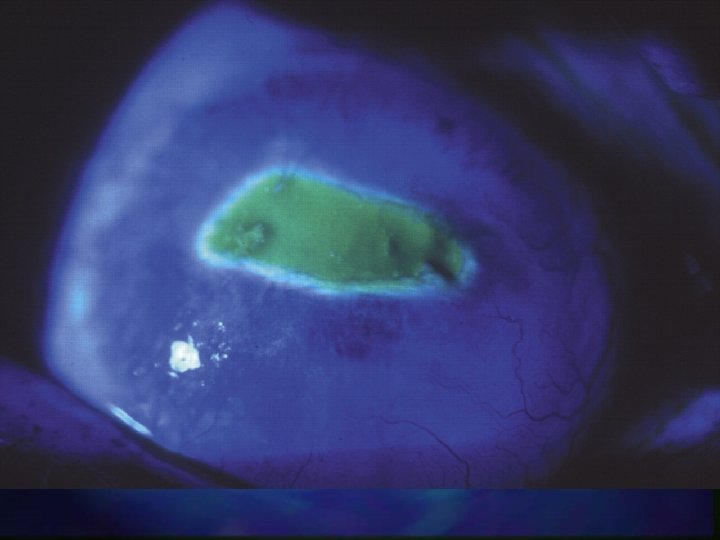

Assessment n History Type of chemical n Alkali/acid n n Examination n Four grades I - IV n Based on corneal clarity n Clear - cloudy = good - poor prognosis n

Grade I • • Clear cornea Limbal ischaemia - nil

Grade II • Cornea hazy but visible iris details • Limbal ischaemia < 1/3

Grade III • No iris details • Limbal ischaemia - 1/3 to 1/2

Grade IV • Opaque cornea • Limbal ischaemia > 1/2